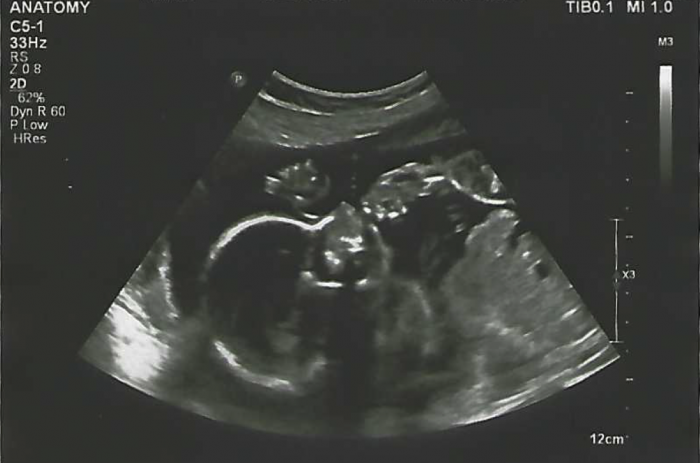

What do medical imaging, geophysical prospecting, and non-destructive testing have in common? They all are examples of imaging techniques that help us see what is inside something without cutting it open (see the cute baby image in Figure 1)

Figure 1: Ultrasound image of PI Graff’s baby in 2020 (photo supplied).